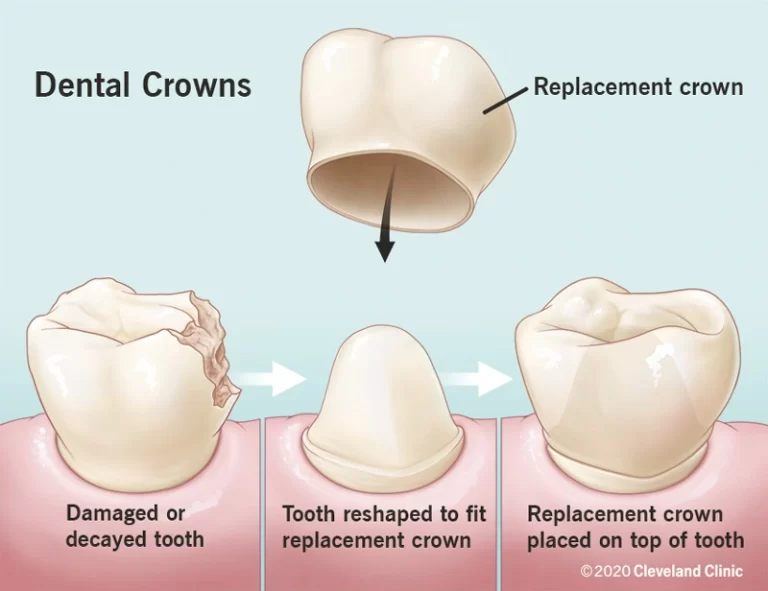

A dental crown is a cap placed over a tooth, serving to restore its shape, size, strength, and aesthetic appearance. Crowns are often recommended when a tooth is significantly decayed, fractured, or has undergone root canal treatment. They can also be used for cosmetic purposes, such as covering discolored or misshapen teeth.

- Protection of damaged teeth: Crowns can help preserve and protect weak or broken teeth.

- Cosmetic enhancement: They can enhance the appearance of a tooth that has discoloration or irregular shape.

- Completing root canal treatment: After the treatment, a crown provides the necessary protection to the treated tooth.

Tooth caps and dental crowns are terms that are often used interchangeably, but they have subtle differences. A tooth cap typically refers to a covering that is placed over a tooth, which is understood to have a more temporary or less extensive application than a dental crown. While dental crowns are custom-made to encase the entire tooth and are generally more robust, tooth caps might not offer the same level of protection or aesthetic enhancement.

Although tooth caps and dental crowns are terms that are often used interchangeably, they represent different dental solutions. A tooth cap typically refers to a covering that is placed over a tooth, which may be a temporary or simpler solution. In contrast, dental crowns are specifically designed to encase an entire tooth, providing significant strength and protection. Crowns are generally made from more durable materials and are used when a tooth is heavily damaged or has undergone root canal therapy. The difference in application and durability is key when discussing your options with a dental professional.